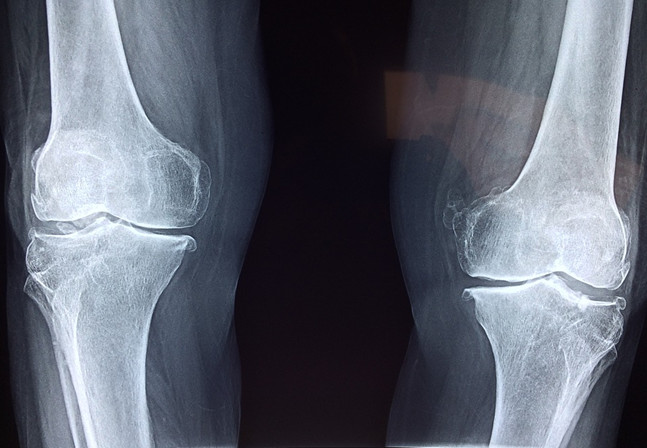

氨糖的全稱是氨基葡萄糖,本質(zhì)上是一種氨基己糖,能夠參與構(gòu)造人體組織和細(xì)胞膜,尤其是對(duì)合成、修復(fù)關(guān)節(jié)軟骨以及關(guān)節(jié)滑液分子的中間物有重要的作用。當(dāng)關(guān)節(jié)軟骨吸收到足夠的氨糖時(shí),軟骨本身就會(huì)變得更強(qiáng)健飽滿,可以在關(guān)節(jié)中牢牢包裹住人體活動(dòng)的硬質(zhì)骨骼,確?;顒?dòng)硬骨在完成相應(yīng)的肢體動(dòng)作時(shí)不與相鄰的骨骼發(fā)生碰撞,并且骨骼之間的接觸面也因?yàn)橛辛孙枬M的軟骨,產(chǎn)生的摩擦并不會(huì)傷害到硬骨本身。

相反,如果身體當(dāng)中缺少氨糖補(bǔ)給的軟骨會(huì)怎么樣呢?在骨骼的摩擦中,原本飽滿健康的軟骨會(huì)被磨損,漸漸地保護(hù)骨骼的作用就會(huì)減弱,失去保護(hù)緩沖的動(dòng)作在完成肢體動(dòng)作時(shí)相互碰撞生痛,也就是許多中老年人遇到腿腳不便的情況了。